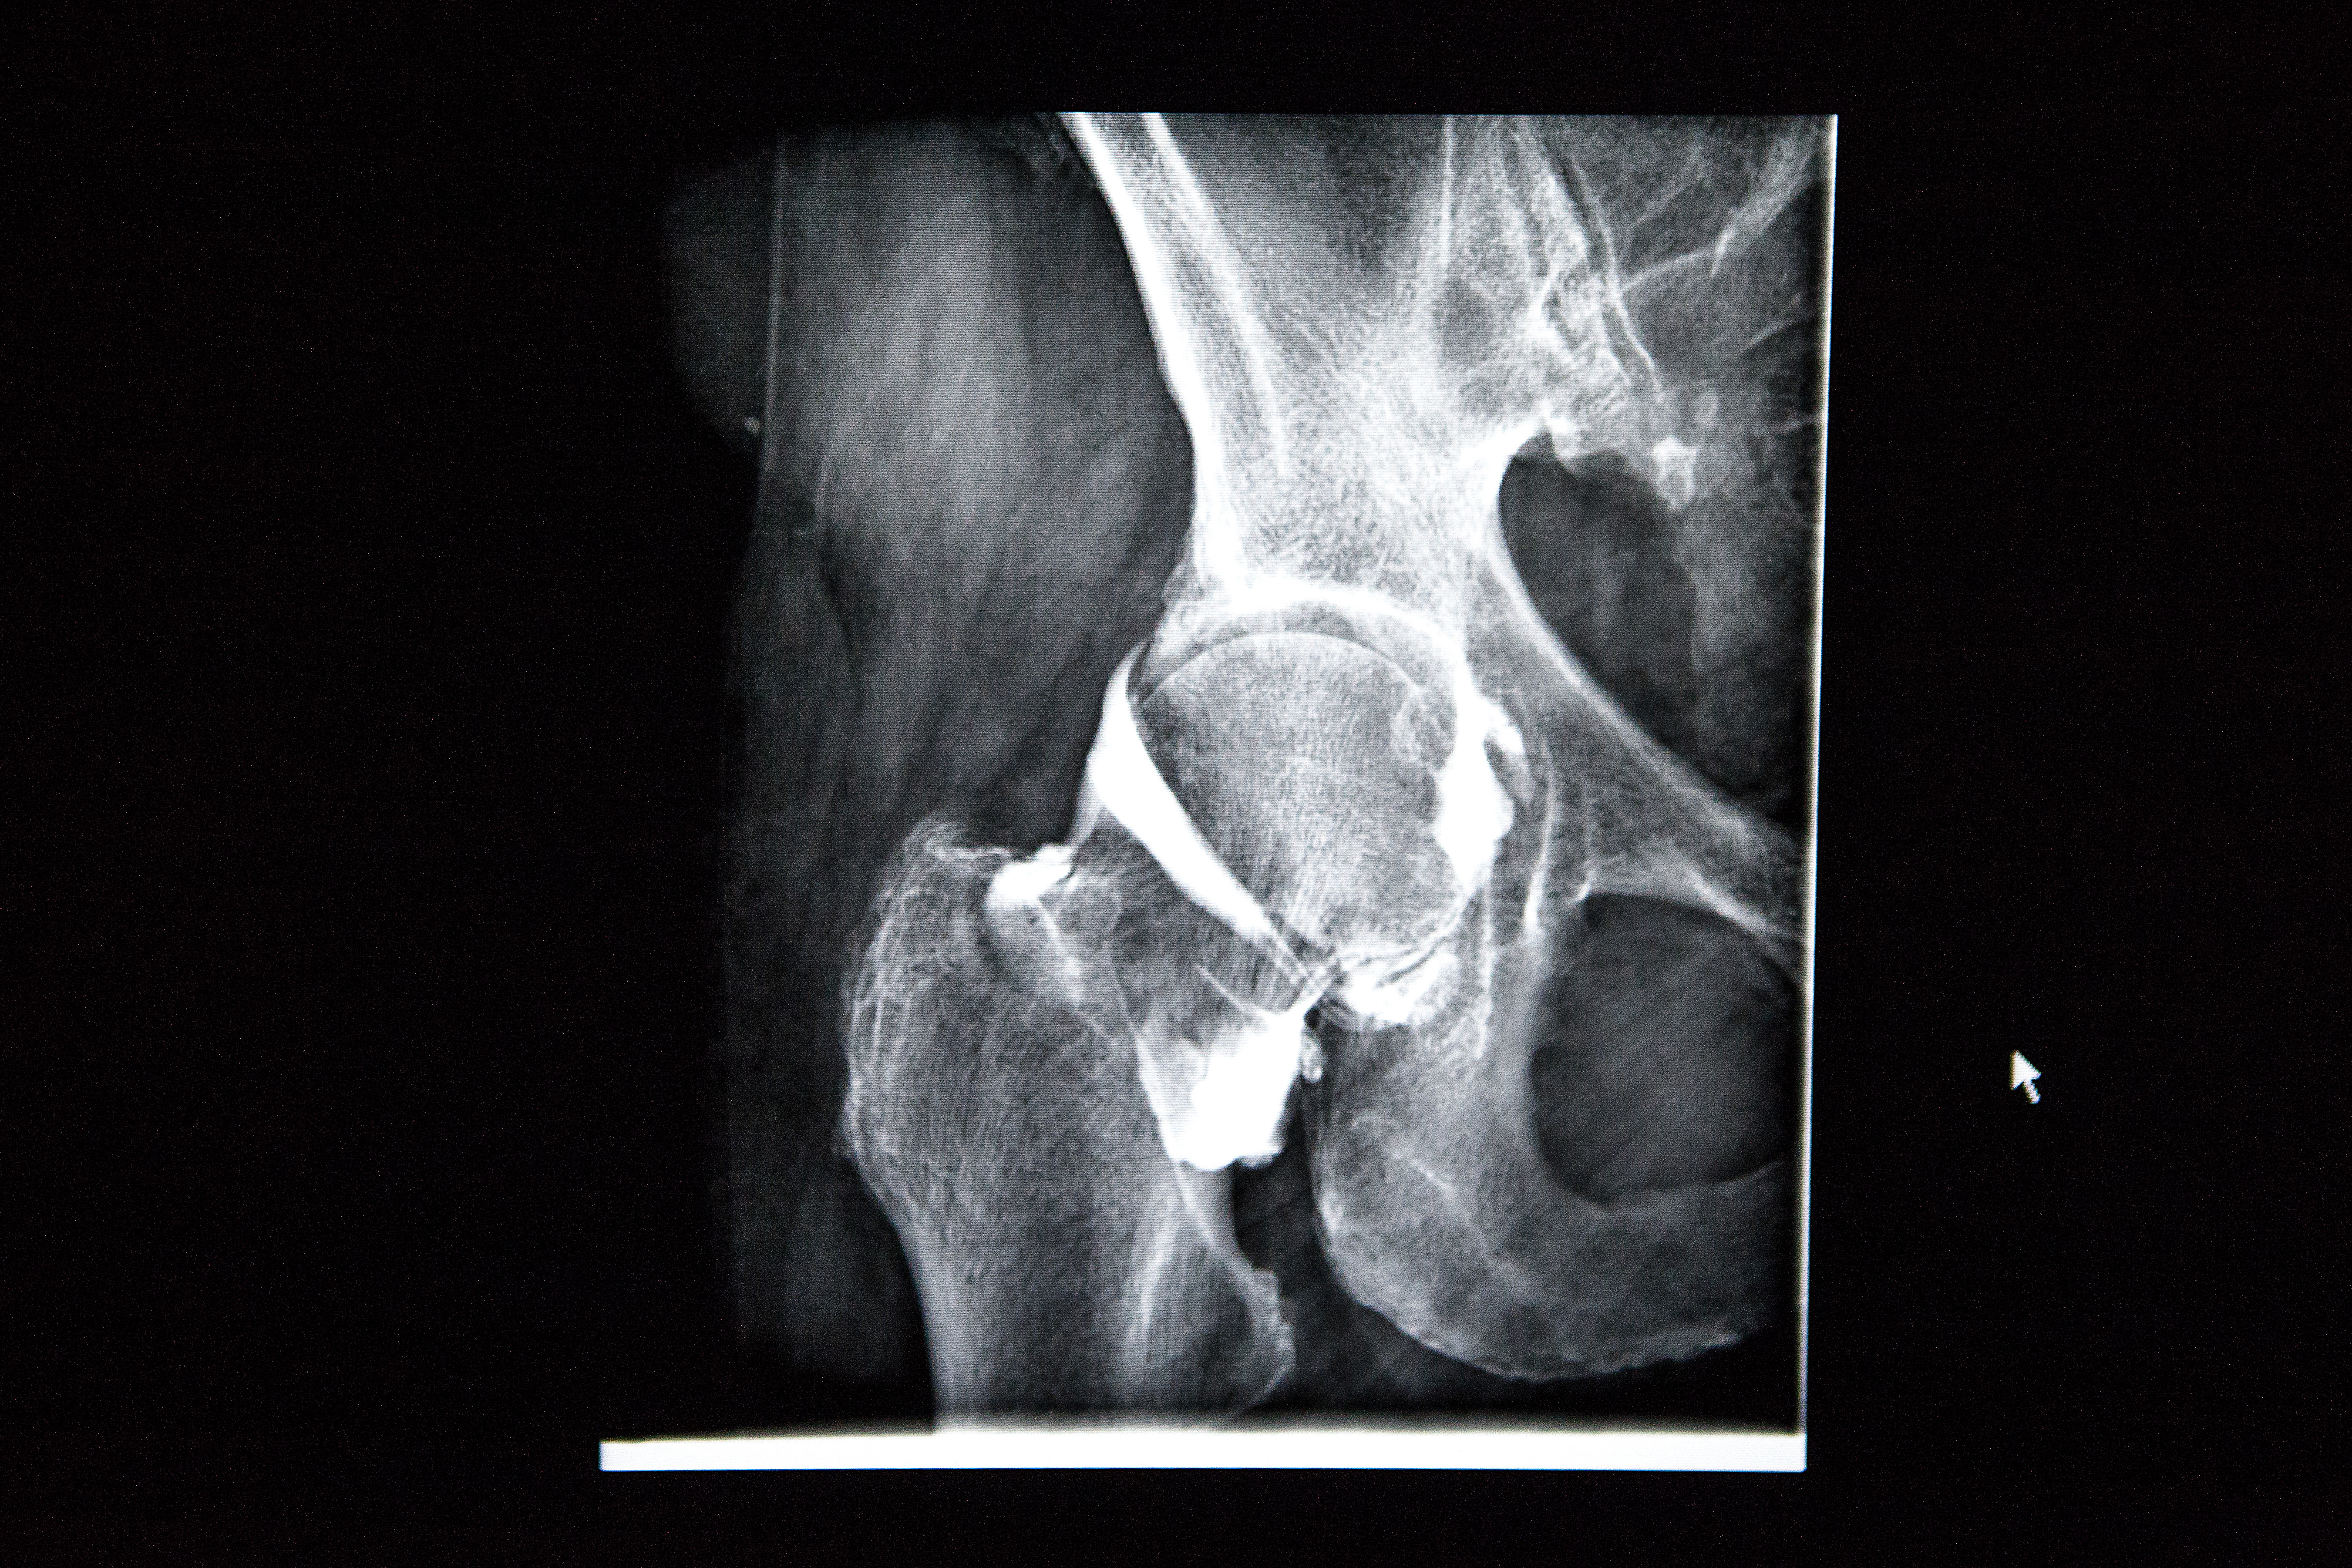

Consider: everything from medicinal side effects, to poor sleeping habits, to concussion history, to minute depreciations in sight and hearing, to a nasty habit of standing up too quickly (which plummets your blood pressure) can contribute to falls in old age. The pros are also capable of catching common culprits as they set in, like osteoporosis.